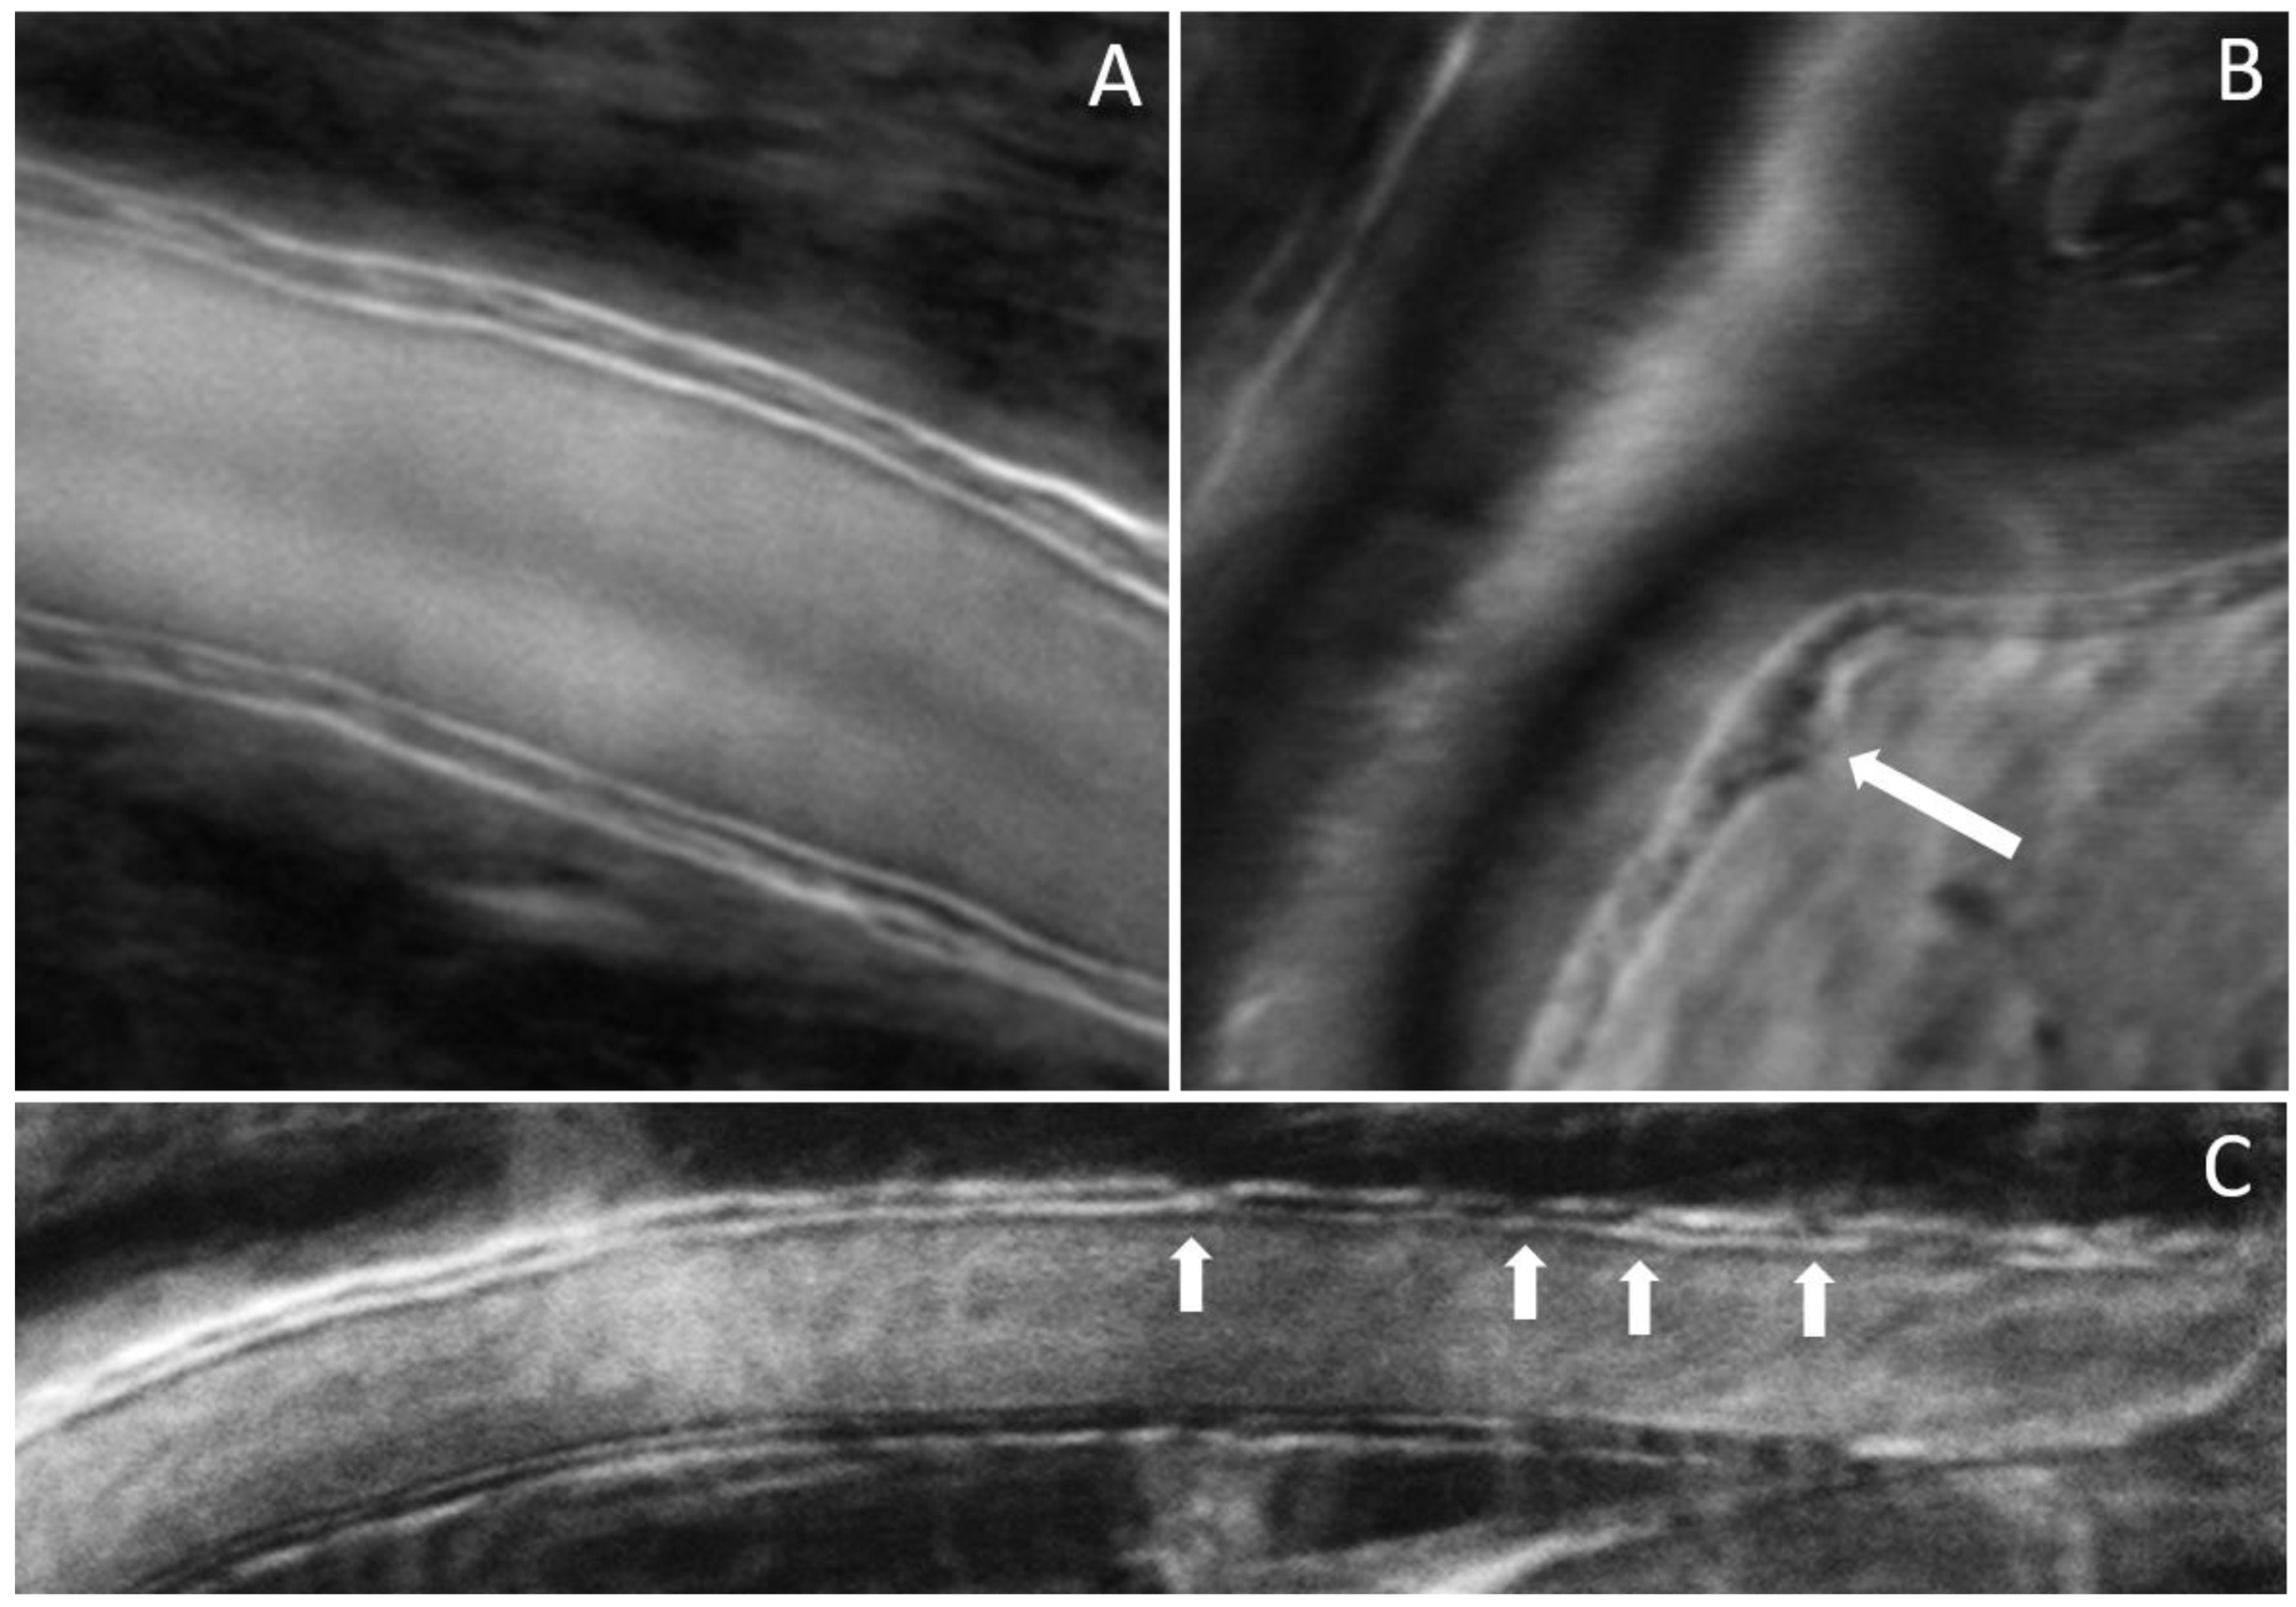

3. Results